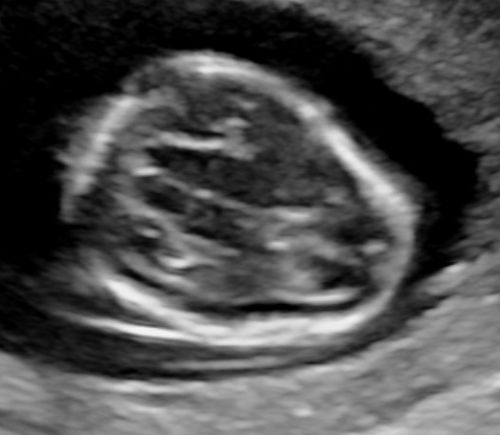

Sono-Online - fetale Fehlbildungen: "Rücken"

Sonoanatomie, Biometrie, Hinweiszeichen & Diagnose von Entwicklungsstörungen, Kasuistiken, ausreichend Zeit für Diskussionen, Fallbeispiele aus der Praxis (Quiz)